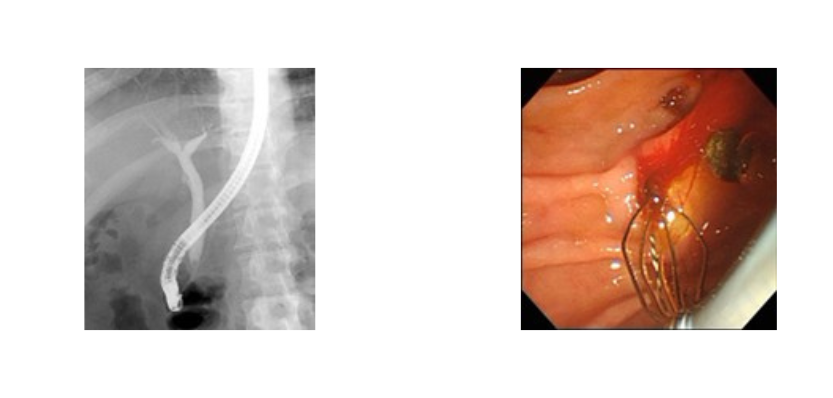

X線透視検査

X線透視撮影装置でX線を連続的に使用しリアルタイムで状態を観察し、撮影を行います。

造影剤を使用した消化管検査(胃透視、注腸造影)や嚥下造影をはじめとし、脱臼や骨折の整復・固定、内視鏡と併用した治療も行います。

主な検査

上部消化管検査

下部消化管検査

ERCP検査(内視鏡的逆行性胆道膵管造影)

口から内視鏡を入れ、胆管や膵管にカテーテルを挿入し、造影剤を使用して胆管・膵管の異常を調べる検査です。検査に続いて胆汁や膵液を外に排出させる治療(ドレナージ治療)を行うことがあります。X線を連続的に照射し、リアルタイムで状態を確認しながら治療を行います。